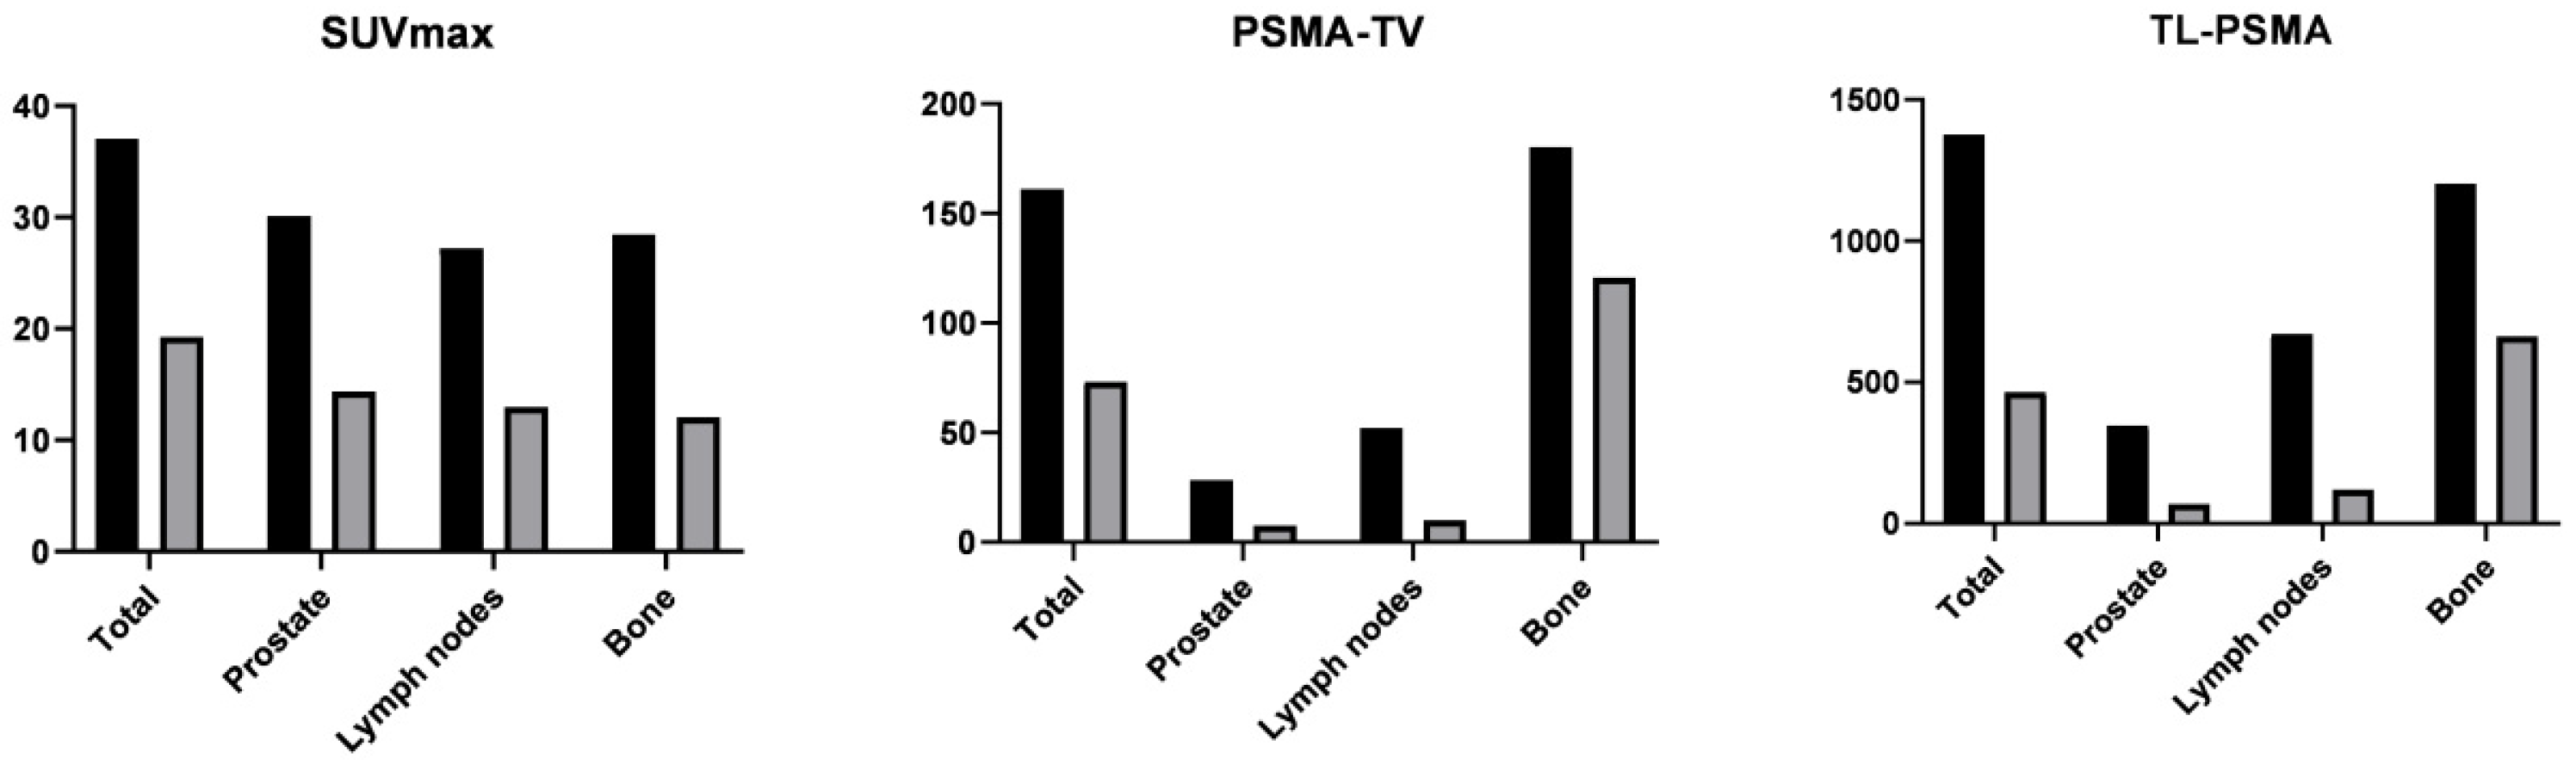

3.4. [68Ga]Ga-PSMA-11 PET/CT Imaging after ADT

| Index | Before ADT | After ADT | Reduction Ratio | p | |

|---|---|---|---|---|---|

| Prostate tumor (n = 30) | |||||

| SUVmax | 30.1 ± 21.4 | 14.4 ± 17.6 | 0.49 ± 0.52 | <0.001 | |

| PSMA-TV | 28.2 ± 34.3 | 7.6 ± 13.3 | 0.50 ± 0.94 | 0.001 | |

| PSMA-TL | 346 ± 519 | 69 ± 159 | 0.70 ± 0.49 | <0.001 | |

| Metastatic lymph nodes (n = 16) | |||||

| SUVmax | 27.2 ± 20.6 | 13.0 ± 24.6 | 0.74 ± 0.37 | 0.001 | |

| PSMA-TV | 52.2 ± 114.3 | 10.1 ± 26.9 | 0.89 ± 0.19 | 0.001 | |

| PSMA-TL | 671 ± 1494 | 120 ± 322 | 0.92 ± 0.14 | 0.001 | |

| Bone metastases (n = 15) | |||||

| SUVmax | 28.5 ± 22.4 | 12.0 ± 14.6 | 0.63 ± 0.34 | 0.001 | |

| PSMA-TV | 180 ± 454 | 121 ± 341 | 0.65 ± 0.37 | 0.001 | |

| PSMA-TL | 1202 ± 2886 | 663 ± 1795 | 0.73 ± 0.35 | 0.001 | |

| Whole-body (n = 30) | |||||

| wbSUVmax | 37.1 ± 22.3 | 19.3 ± 22.3 | 0.47 ± 0.43 | <0.001 | |

| wbPSMA-TV | 161 ± 431 | 73 ± 248 | 0.54 ± 0.80 | <0.001 | |

| wbPSMA-TL | 1375 ± 2945 | 464 ± 1374 | 0.72 ± 0.37 | <0.001 | |